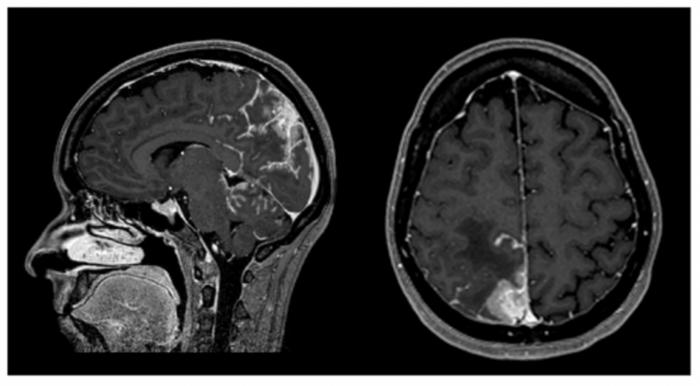

Figure 1: CE MRI at BM and LMC initial moment of diagnosis.

Heterogeneous space-occupying lesion (right posterior parietal-parasagittal cortico-subcortical area), with vasogenic edema and sulcal effacement, compatible with a BM lesion, along with pachymeningeal carcinomatosis (right next to the first described BM).